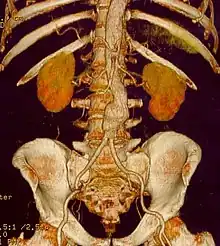

Abdominal aortic aneurysms (AAAs) are more common than their thoracic counterpart. One reason for this is that elastin, the principal load-bearing protein present in the wall of the aorta, is reduced in the abdominal aorta as compared to the thoracic aorta. Another is that the abdominal aorta does not possess vasa vasorum, the nutrient-supplying blood vessels within the wall of the aorta. Most AAA are true aneurysms that involve all three layers (tunica intima, tunica media and tunica adventitia). The prevalence of AAAs increases with age, with an average age of 65–70 at the time of diagnosis. AAAs have been attributed to atherosclerosis, though other factors are involved in their formation.[7]

The risk of rupture of an AAA is related to its diameter; once the aneurysm reaches about 5 cm, the yearly risk of rupture may exceed the risks of surgical repair for an average-risk patient. Rupture risk is also related to shape; so-called "fusiform" (long) aneurysms are considered less rupture-prone than "saccular" (shorter, bulbous) aneurysms, the latter having more wall tension in a particular location in the aneurysm wall.[9]

The diagnosis of an abdominal aortic aneurysm can be confirmed by the use of ultrasound. Rupture may be indicated by the presence of free fluid in the abdomen. A contrast-enhanced abdominal CT scan is the best test to diagnose an AAA and guide treatment options.[10]